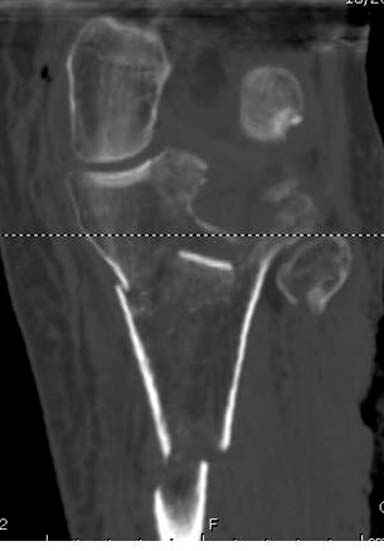

Отдельные переломы тибиал плато и перелом проксимальной трети большеберцовой кости отличаются от переломов тибиал плато с вовлечением диафиза. Здесь перелом тибиал плато типа Schatzker VI, полученный в результате высокоэнергетической травмы. Перелом метафиза образовал отрыв суставной поверхности от диафиза с вовлечением медиального и латерального мыщелков. Двухмыщелковые переломы из-за укрочения опасны развитием компартаментального синдрома, повреждением латерального мениска и связок.

На вашем место я бы подождал с фиксацией до готовности кожных покровов, и за это время можно было подобрать соответствующий фиксатор, т.е более длинная пластина снаружи и медиальная пластина на апексе перелома как подпорка. Здесь приемлем как раз минимальный доступ.

Если там действительная импрессия, пустое место без структуральных заполнителей, кость или синтетические материалы, не восстановится, а образуется коллапс, и ось конечности поведет после нагрузки. Кроме того там возможно "болт стяжка"?, в медиальной стороне выступает за кортекс, можно было укоротить! Потом создается впечатление, что не соответствуют мыщелки большеберцовой и бедренной костей? Покажите снимок.

Ваша упорство с минимальными данными защищаться забавляет, и пока не все убедились в Вашей правоте. Для нормальной защиты необходимы аргументированные доказательства исследованиями. КТ сканы и прицельно сделанные снимки коленного сустава, а так все аргументы - не более чем "моя фиксация, мне нравится". Без этих доказательств пока только Ваше упорство.....

Здесь пару случаев для сравнения,...в первых 1-4 слайдах метод фиксации одним фиксатором, как видно после 8 месяцев сохранилась ось. С 5 по 9 вариант двумя пластинами...